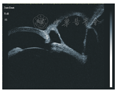

患者男,57岁。2014年1月于河南省立眼科医院就诊,1个月前,自觉左眼异物感,视力下降,并发现左眼泡样隆起物,来我院就诊。追问病史,患者30年前左眼曾被扫帚击伤,未行手术治疗,全身及局部应用药物治疗,视力稍有下降。本次入院检查:视力:右眼0.8,左眼0.1;眼压:右眼16 mmHg,左眼15 mmHg。左眼鼻下方球结膜可见巨大泡样隆起,壁薄,6点至9点位角巩膜缘处可见巩膜葡萄肿,余角膜透明,前房中深,瞳孔呈梨形,向鼻下方移位明显(图1)。左眼UBM检查角膜回声清晰,中央前房深2.4 mm,瞳孔向鼻侧移位,8点位角巩膜缘处连续性中断,断口直径约0.57 mm,缺损处上方少部分向前房内弯曲,对应处见巨大结膜滤过泡,与前房沟通,呈分叶状(图4)。左眼B超见玻璃体混浊。根据患者外伤史及检查所见,诊断为:左眼前巩膜葡萄肿伴巨大滤过泡,入院行异体巩膜移植术。手术方法:因滤过泡与前房沟通,为避免切开滤过泡时眼压骤降,先行前房穿刺,降低眼压,沿角膜缘剪开鼻下方球结膜,暴露巩膜葡萄肿,发现8点处角巩膜缘穿孔,虹膜嵌顿,与周围组织粘连较重,去除虹膜表面结膜上皮,回纳部分虹膜,板层剖切穿孔周围巩膜,取相应大小异体巩膜植片间断缝合于巩膜植床。术后第3天:球结膜充血水肿,角膜透明,前房中深,瞳孔不规则,直径约4 mm(图2)。复查UBM见左眼角膜回声清晰,中央前房深2.6 mm,角巩膜未探及低回声区(图5)。术后取剖切巩膜病理检查示:巩膜穿孔,可见虹膜组织粘连,符合葡萄肿改变(图3)。